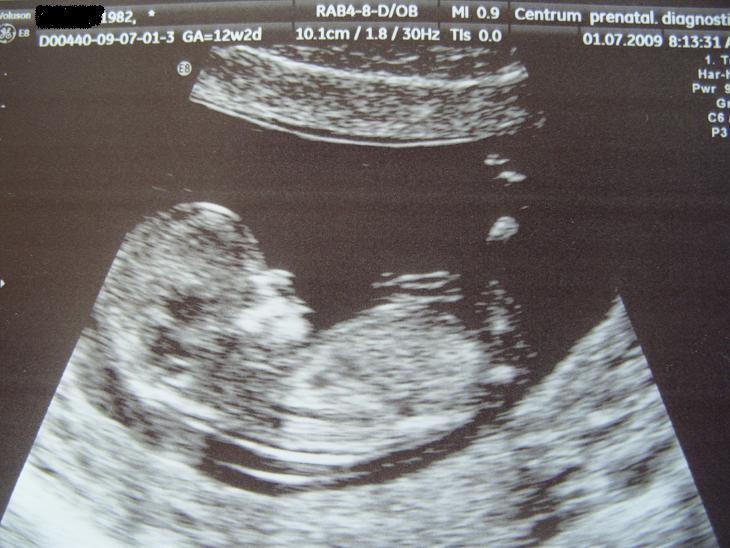

12tt+2